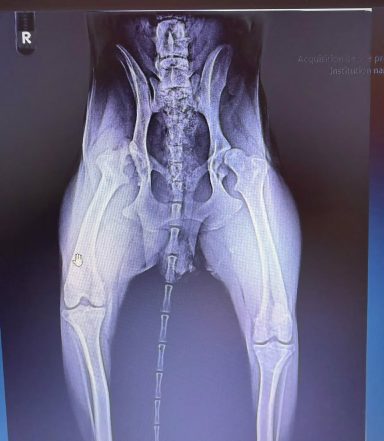

Lilo wurde aus schlechter Haltung gerettet. Bei der Untersuchung wurde eine angeborene beidseitige Hüftgelenksdysplasie festgestellt.

Aktuell hat sie noch keine Schmerzen, könnte aber später eine Operation benötigen.

weitere Informationen: angeborene Hüftgelenkdysplasie beidseitig